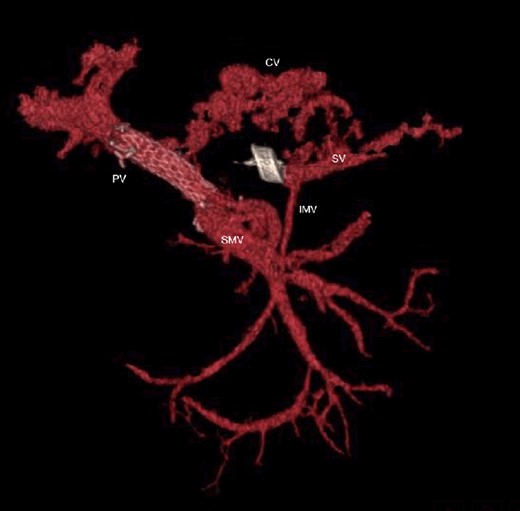

The abdominal exploration was difficult due to significant inflammatory adhesions, which can be attributed to the presence of a pancreatic fistula and the delay of relaparotomy. There was no bleeding observed within the abdominal cavity, and no bleeding was seen from the multitubular drain during the exploration. We hypothesized that the bleeding was of venous origin caused by drain-induced recurrent erosion of peripancreatic vessels, resulting in intermittent bleeding, and that removing drains could help in attaining venous hemostasis. As a result, it was decided to remove the drains. However, this resulted in a significant hemorrhage via the drain orifice. Due to failure to identify the exact origin of bleeding and without the possibility of completion pancreatectomy, we performed a damage control procedure by packing through the drain orifice. This successfully stopped the bleeding. A postoperative CT scan located the packing sponges anterior to the spleno-mesenteric confluence (SMC) (Fig. 2). A percutaneous transhepatic portography showed an irregular aspect of the SMC, without thrombi or contrast extravasation (Fig. 3). After consulting with the interventional radiology team, we placed a cover stent (Fluency™ Bard, Murray Hill, USA) in the SMC (Fig. 4). Two days later, we removed the packs, and a massive hemorrhage recurred, necessitating a new packing. The stent was not seen on a subsequent CT scan. We then performed an endovascular procedure to exclude the segment of the irregular SMC. An Amplatzer™ vascular plug (Abbott Vascular, Santa Clara, USA) was placed in the splenic vein, extending distally to just surpass the inferior mesenteric vein (IMV) insertion (Fig. 5). A cover stent was subsequently deployed in the portal vein, extending distally to the superior mesenteric vein. This allowed for the exclusion of the splenic vein segment that lies between the inferior mesenteric vein insertion point and the spleno-mesenteric confluence (Fig. 5). The packing sponges were removed 10 days later without bleeding recurrence, and the patient finally showed clinical improvement. After 3 years, the stent was visible and permeable on a follow-up CT scan. The scan showed development of venous collaterals, which drain the distal splenic vein and inferior mesenteric vein through the lesser omentum (Fig. 6).

CT scan after other interventional radiology with plug in the splenic vein and cover stent in the superior mesenteric vein. PV portal vein, SMV superior mesenteric vein, SV splenic vein, IMV inferior mesenteric vein.